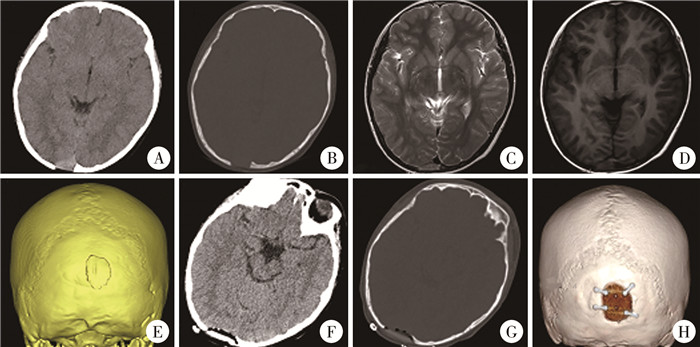

二、治疗结果及术后病理检查结果术后病理检查证实为LCH 5例(图 1),非霍奇金B淋巴母细胞性淋巴瘤1例(图 2),骨纤维结构不良1例(图 3),颅骨筋膜炎1例,骨瘤1例。1例骨纤维结构不良及1例淋巴瘤为大部切除病变,其余7例为全切除病变。修补材料均采用PEEK。所有患儿术中无一例静脉窦损伤、脑损伤等并发症。术后无一例出现出血、感染、切口愈合不良等并发症。1例术后出现皮下积液,予消毒后局部穿刺抽吸积液并加压包扎,于出院前积液消退。

图 3 1例骨纤维结构不良患儿影像学资料 Fig.3 Imaging data of a child with OFD 注 A:术前外观,见左侧额顶及眉弓异常凸起;B:术前颅脑CT骨窗三维重建;C:术前颅脑MRI-T1增强矢状位;D:术前颅脑CT轴位骨窗;E:术后外观,见左侧额顶及眉弓形态正常;F:术后颅脑CT骨窗三维重建;G:术后颅脑CT轴位骨窗;H:随访时颅脑CT轴位骨窗 |

骨纤维结构不良存在自限性,在青春期结束后可能停止进展。少年及儿童的单纯颅骨骨纤维结构不良,若未造成颅神经压迫症状且未引发美观问题,原则上首选随诊[12]。若随诊期肿物增长迅速,或出现颅神经压迫症状,或出现血清碱性磷酸酶迅速增高等明显进展表现,可考虑积极手术,但仍以神经减压或部分切除达到美观为目的[5, 12-13]。术后可选择临床观察,或使用唑来膦酸缓解病情进展[12]。若病变位于颅盖骨,凸出明显且影响美观者,可积极手术[5, 12-13]。本组1例存在手术指征,虽然跨过上矢状窦,但术中发现与静脉窦并无明显粘连,因此,术中切除骨病变及保护静脉窦相对容易。